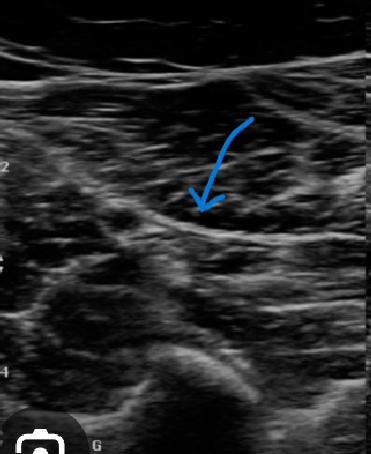

Is the soleal muscle above or below the echogenic line?

Below